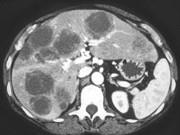

问题 男,54岁,患者1年前行结肠癌手术,癌胚抗原增高,影像检查如图,最可能的诊断是()

选项 A.多发结节性肝癌 B.结肠癌肝转移 C.多发性肝脓肿 D.多发性肝囊肿 E.肝淋巴瘤

答案 B